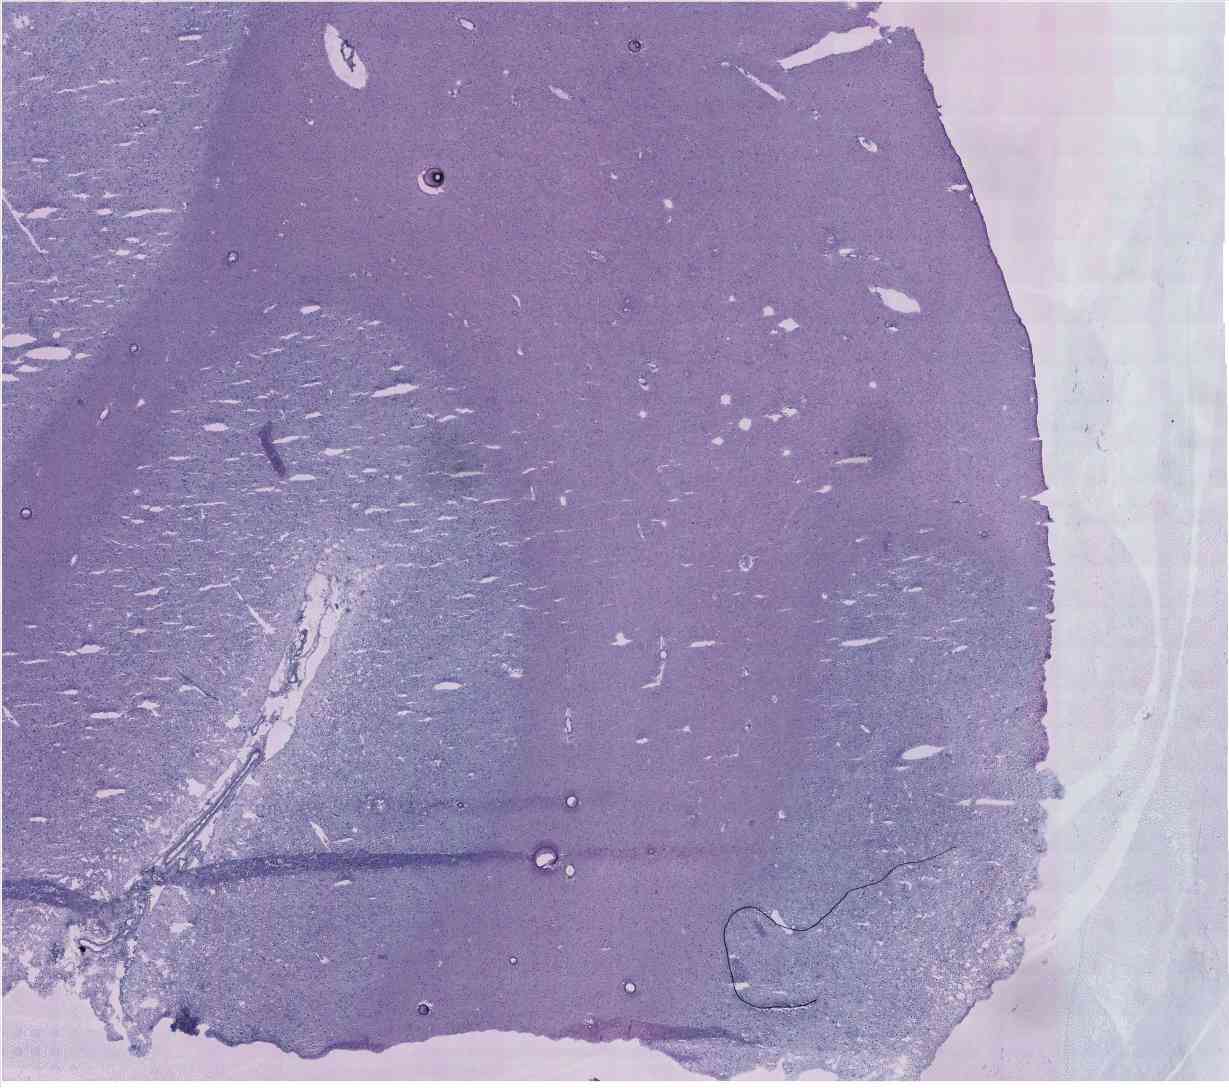

Chip 067 Well E2